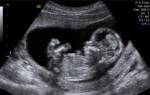

Вероятность ошибки на УЗИ определения пола ребенка может быть и в неточном определении половых признаков. Так, «увидеть» мальчика можно по половому члену и мошонке, а у девочки должны быть видны большие половые губы.

Зачастую врач может принять пальцы ребенка или пуповину за половой член, а отекшие половые губы девочки (случается часто) тоже можно принять за мошонку.

Кроме этого, плод может «спрятать» свои прелести и сжать плотно ножки, а врач подумает, что это девочка.

Не очень часто, но все-таки бывают ошибочные определения половой принадлежности детей к мужскому роду из-за принятия пуповинной петли, а также пальцев рук ребенка за половой член. Отеки половых губ девочки также путают с мошонкой.